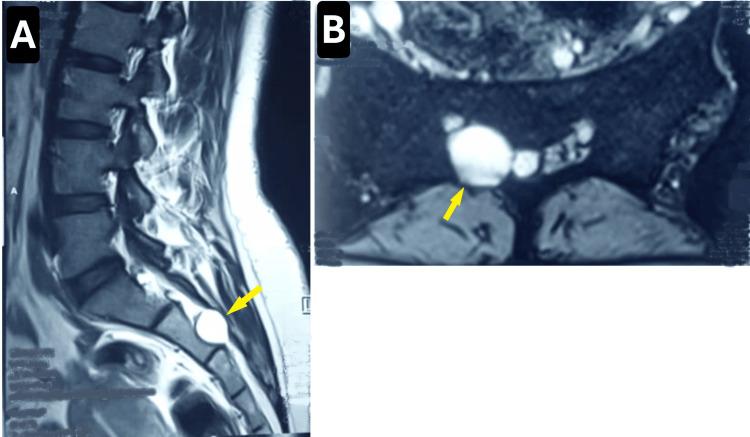

Tarlov cysts, also known as perineural cysts, are cerebrospinal fluid-filled sacs that typically form near the dorsal root ganglion, most commonly at the sacral levels S2 and S3. While most are incidentally identified on imaging, symptomatic cysts, particularly in the lower lumbar and sacral regions, can produce neurological symptoms similar to those of a herniated disc and may have a clinically significant impact on urogenital function. We present the case of a 38-year-old woman with a long-standing history of chronic pelvic dysfunction characterized by recurrent urinary tract infections, urinary incontinence, and perineal hypoesthesia, all of which significantly impacted her quality of life. Imaging studies revealed a Tarlov cyst involving the right S2 nerve root. Surgical intervention, consisting of cyst decompression and nerve root repair, resulted in substantial symptom improvement. Although most Tarlov cysts are incidental findings, they can cause debilitating symptoms in select cases. The decision to pursue surgical intervention is complex, yet it can yield remarkable improvements, as demonstrated by our patient's outcome. However, the literature also highlights the potential for recurrence. This case underscores the importance of considering Tarlov cysts in patients presenting with unexplained chronic pelvic, urinary, or sexual dysfunction. While surgical intervention may provide significant relief in carefully selected cases, it also emphasizes the necessity for early recognition and timely management.

塔尔洛夫囊肿,也称为神经周囊肿,是充满脑脊液的囊,通常在背根神经节附近形成,最常见于骶骨水平的S2和S3。虽然大多数囊肿是在影像学检查中偶然发现的,但有症状的囊肿,特别是在腰骶部区域,可产生与椎间盘突出症相似的神经症状,并可能对泌尿生殖功能产生临床上的重大影响。我们报告一例38岁女性,有长期慢性盆腔功能障碍病史,其特征为反复尿路感染、尿失禁和会阴感觉减退,所有这些均严重影响了她的生活质量。影像学检查显示一个累及右侧S2神经根的塔尔洛夫囊肿。手术干预包括囊肿减压和神经根修复,使症状得到了显著改善。虽然大多数塔尔洛夫囊肿是偶然发现的,但在某些情况下它们可导致使人衰弱的症状。决定是否进行手术干预很复杂,但正如我们患者的结果所示,手术可以带来显著改善。然而,文献也强调了复发的可能性。该病例强调了在出现不明原因的慢性盆腔、泌尿或性功能障碍的患者中考虑塔尔洛夫囊肿的重要性。虽然手术干预在精心挑选的病例中可能会带来显著缓解,但它也强调了早期识别和及时处理的必要性。